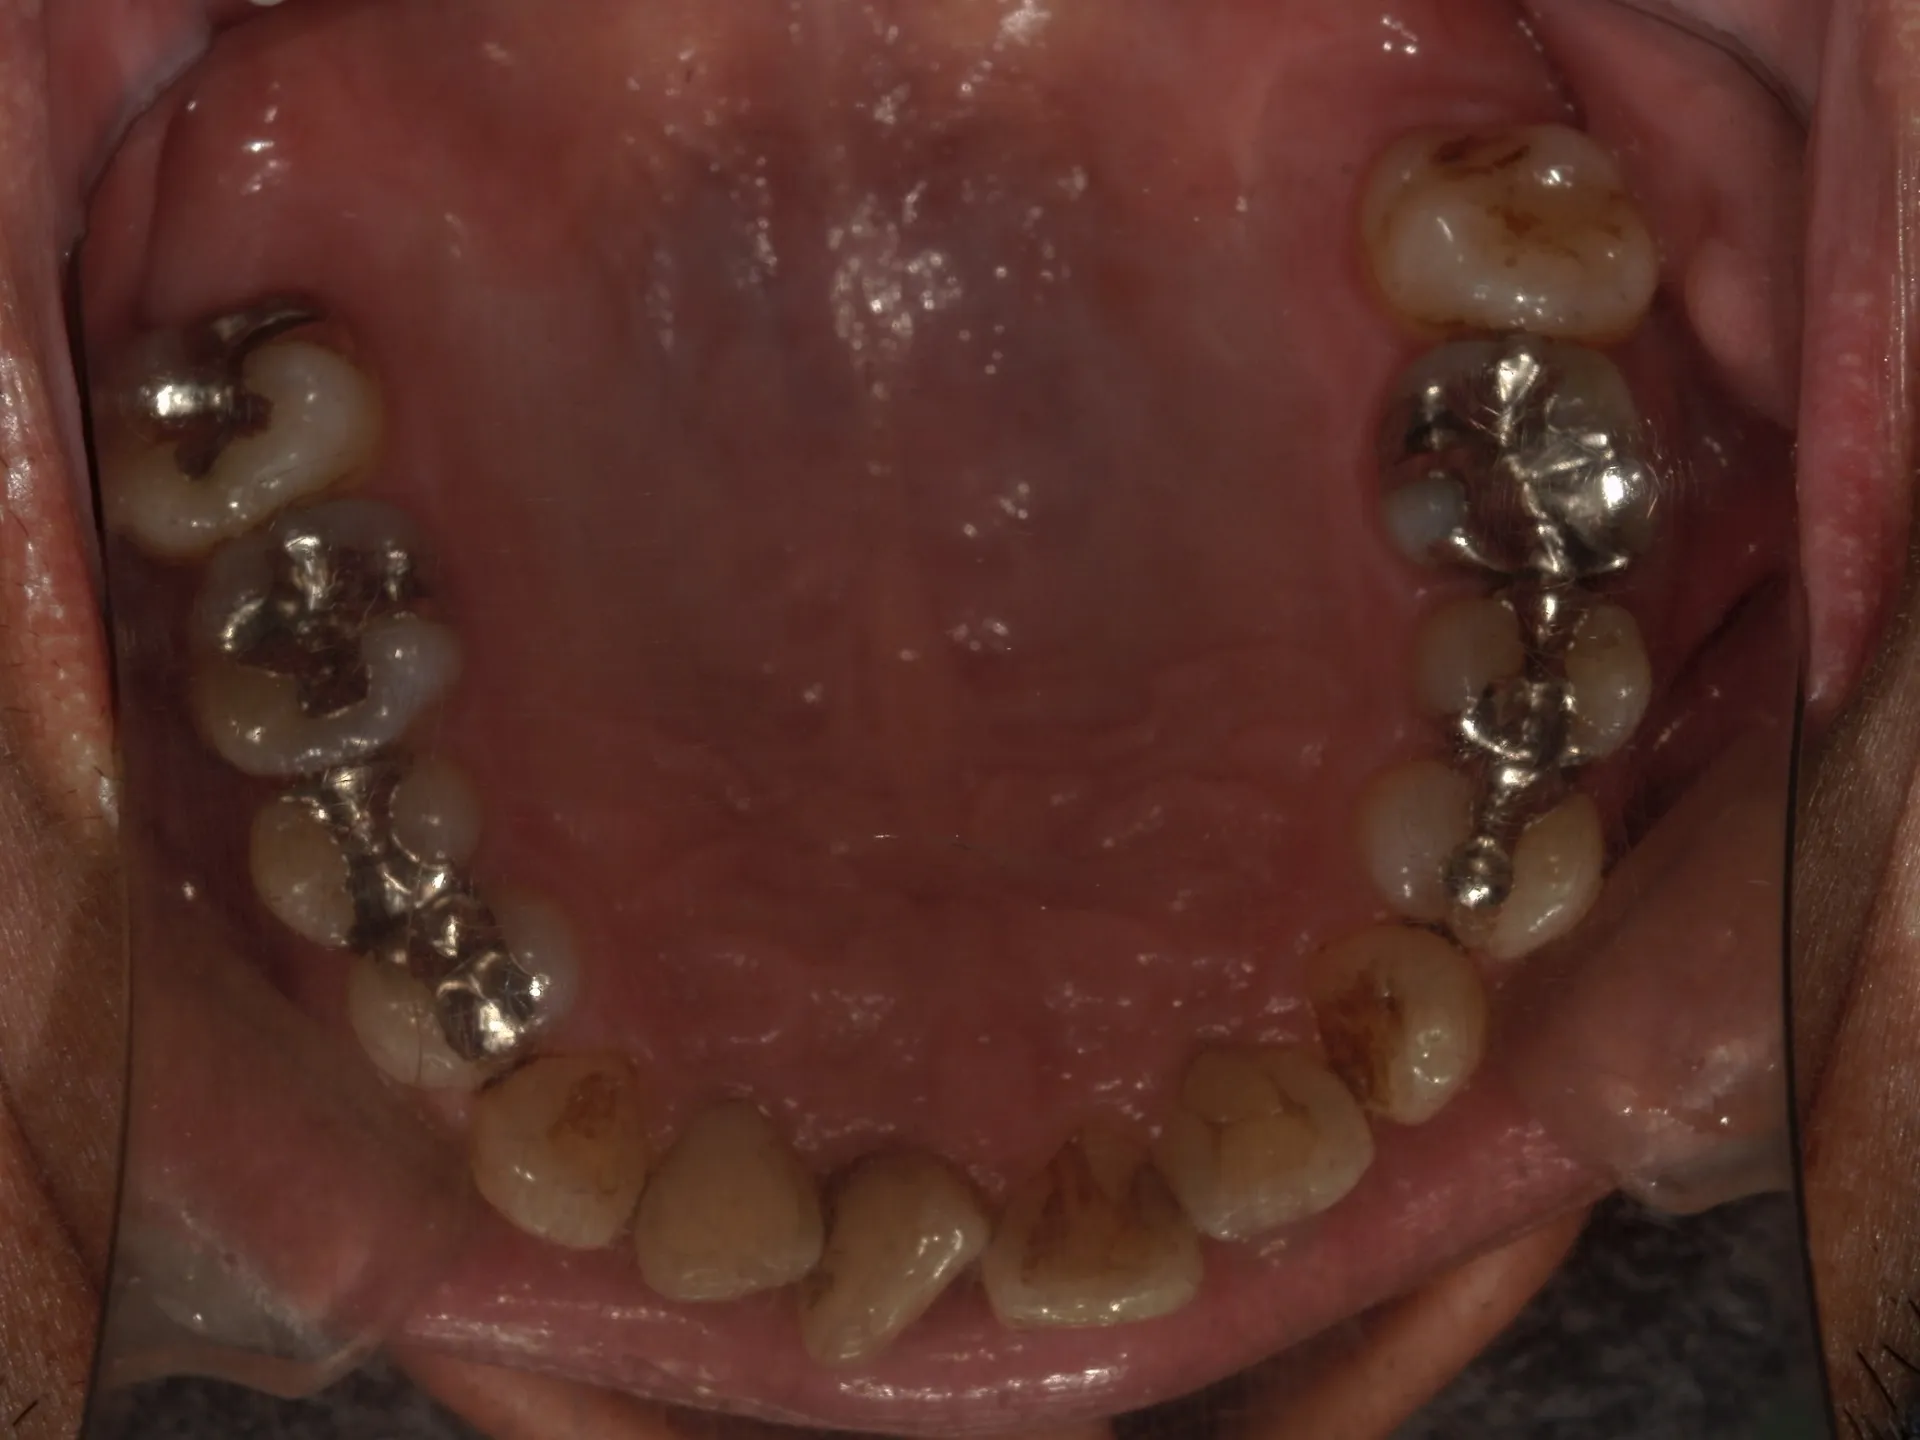

① 保険の歯の掃除(スケーリング・ルートプレーニングなど)

目的:歯周病(歯肉炎・歯周炎)の治療、進行予防

対象:歯石やプラークの除去

範囲:医療行為として認められた範囲のみ(歯石やプラークがついていないと保険は算定できません)

内容:歯周ポケット検査を行い、その後超音波スケーラーや手用スケーラーで歯肉縁上・縁下の歯石を取る

② 自費のPMTC(Professional Mechanical Tooth Cleaning)

目的:予防、見た目の改善、仕上げ磨き

対象:歯石があるなしに関係なく、バイオフィルムやステインを徹底的に除去